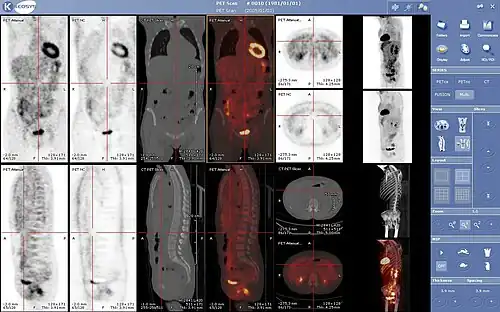

Normal whole body PET/CT scan with FDG-18. The whole body PET/CT scan is commonly used in the detection, staging and follow-up of various cancers. -

Abnormal whole body PET/CT scan with multiple metastases from a cancer. The whole body PET/CT scan has become an important tool in the evaluation of cancer.